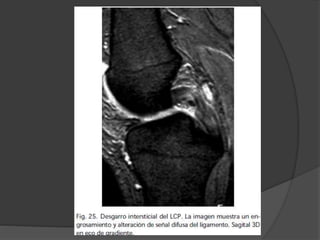

LCP

 Representa de 5-20% de todas las lesiones ligamentosas de

la rodilla.

 1.- Rotura es más frecuente en su tercio medio

 2.- Avulsiones femoral y tibial.

 El LCP normal es hipo-intenso en todas las secuencias homogéneo

 Su morfología del LCP depende

 Grado de flexión de la rodilla

 Integridad del LCA y del resto de estructuras de soporte

 Con la rodilla en extensión o con un grado mínimo de flexión, el

ligamento muestra un margen posterior convexo

 Si la rodilla está en flexión de más de 10º, el ligamento se tensa y

muestra un grosor ligeramente menor que en extensión.

 Roturas parciales

 Area hiperseñal y fibras ligamentosas visibles en todo el

trayecto del ligamento.

LCP Las roturas por avulsión

 Afectan generalmente a la inserción tibial

 El fragmento óseo tiene un desplazamiento mayor que en las

avulsiones del LCA

 Extenso edema y hemorragia subcondral en el lugar de la

avulsión.